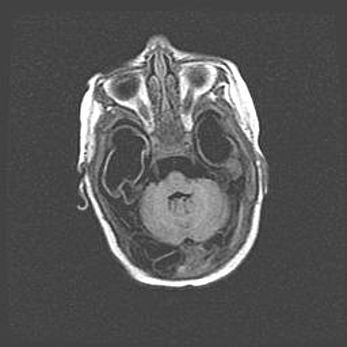

Мальформация Денди-Уокера. Киста задней черепной ямки.

Агенезия мозолистого тела.

Возраст: 2,5 месяца

Вес: 2420 г

Пол: женский

Окружность головы: 37 см

Срок гестации: 32 недели

Мальформация Денди—Уокера — редкий вид патологии ЦНС, представляющий собой врожденный порок развития каудального отдела ствола и червя мозжечка, ведущий к неполному раскрытию срединной (Мажанди) и латеральных (Лушка) апертур IV желудочка мозга. Для этогно синдрома характерна триада симптомов: гипотрофия червя мозжечка и/или полушарий мозжечка, кисты задней черепной ямки, гидроцефалия различной степени. В 70% случаев порок сочетается и с другими аномалиями головного мозга, в частности с агенезией мозолистого тела.